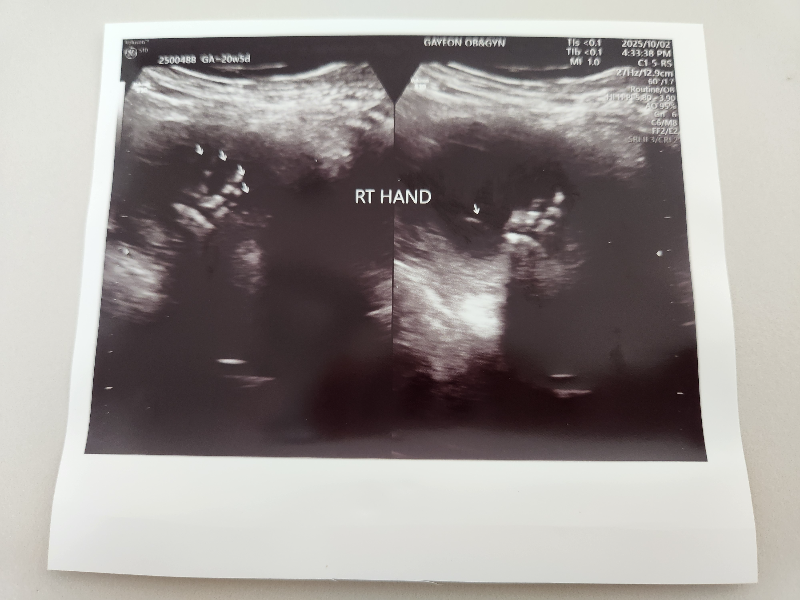

오른쪽 손 왼쪽 손 손가락을 다 확인합니다.